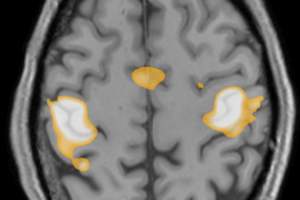

Nonobstructive Hydrocephalus – Normal Pressure Hydrocephalus

The most common cause for enlargement of the ventricles is ex vacuo dilation due to atrophy of the cerebral parenchyma. It is important to distinguish ex vacuo ventricular dilation from true enlargement... Read more »